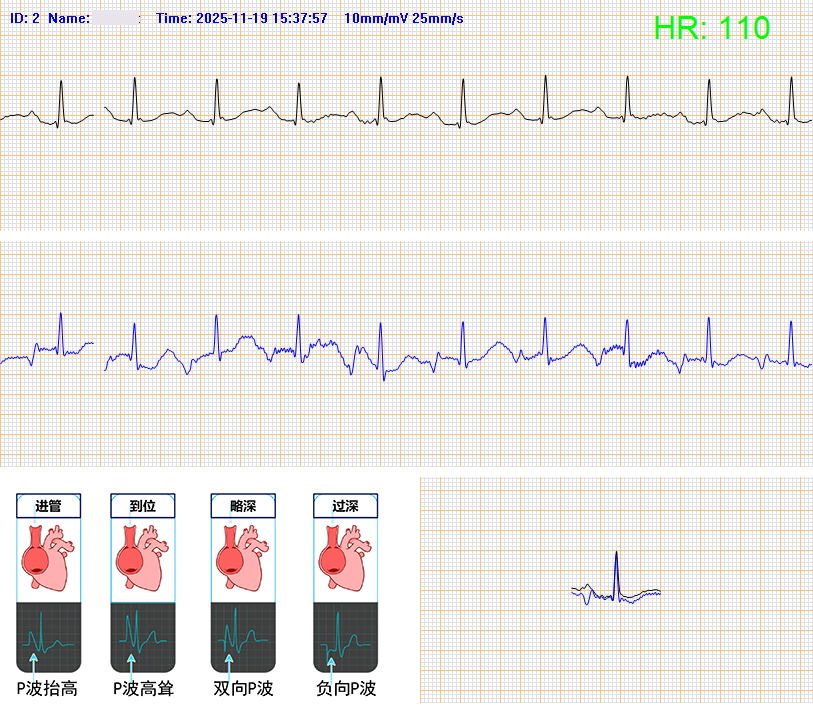

该患者因肺肿瘤且患有严重的上腔静脉压迫综合征,导致胸部以上的血液回流心脏的主要通道被压迫堵塞,传统的上肢PICC置管路径完全无法实施。面对这一棘手难题,静脉治疗学组团队对患者病情进行充分评估,在介入血管外科李俊杰主任指导下,决定采用下肢股静脉穿刺隧道式PICC置管术。 尽管下肢股静脉穿刺优势明显,但下肢穿刺点离心脏更远,路径更复杂,对操作者有极高的技术要求。静脉治疗学组凭借过硬的专业本领,运用腔内心电导联技术进行实时定位,成功将导管置入最佳位置,为患者后续治疗提供了一条“安全生命通道”。 与上肢穿刺相比,下肢股静脉路径展现出了独特的三大优势: 1.突破禁忌症:为上腔静脉综合征等上肢无法穿刺的患者提供了唯一可行的中心静脉通路方案,是真正的“生命替补通道”。 2.提升安全性:隧道式植入导管显著降低导管相关性感染和导管移位的风险,提升了长期带管的安全性与稳定性。 3.血管选择更优:下腔静脉血管粗直,血流量大,能有效避免药物对血管壁的刺激,尤其适合需要长期、高效输注药物的肿瘤患者。 下肢隧道式PICC置管术的成功实施,为构建“全身血管通路”打通了关键一环。此项技术不仅突破了传统PICC的局限,更推动了静脉治疗技术的跨越式发展。下一步,静脉治疗学组将继续致力于前沿技术的探索与引进,着力提升复杂疑难血管通路的解决能力。以更优质、安全、高效的护理服务,全力守护患者健康。